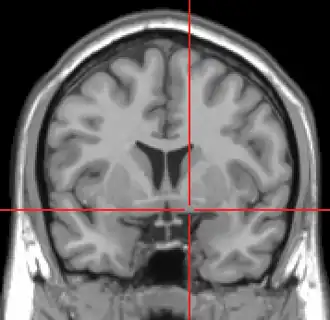

Een MRI-scan van de hersenen, gezien van voren, met de locatie van de nucleus basalis aangegeven. | ||||